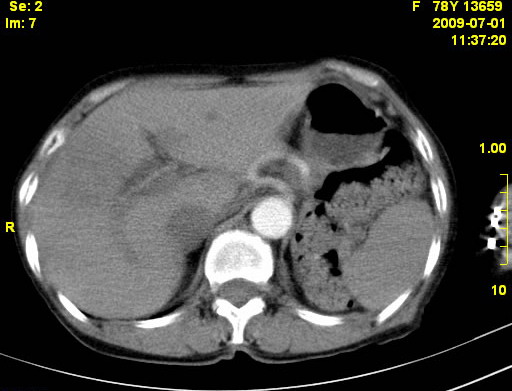

以下是引用zjzjr在2009-7-3 11:02:00的发言:[br]动脉期不均匀强化,门脉期及延迟期强化明显,肝门部见肿大淋巴结影,肝内胆管扩张.考虑肝右叶前段胆管细胞癌伴肝门淋巴结转移,胆内胆管扩张.慢性胆囊炎.

以下是引用dsl555在2009-7-4 10:59:00的发言:[br]考虑肝右叶前段胆管细胞癌伴肝门淋巴结转移,胆内胆管扩张.慢性胆囊炎. [br][br]支持。